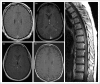

Recent findings: Affected patients present with symptoms of one or more of meningitis (headache and neck ache), encephalitis (delirium, tremor, seizures, or psychiatric symptoms), and myelitis (sensory symptoms and weakness). Optic disc papillitis (blurred vision) is common. CNS inflammation is evident in characteristic T1 postgadolinium enhancement of GFAP-enriched CNS regions, and lymphocytic cerebrospinal fluid (CSF) white cell count elevation. CSF is more reliable than serum for GFAP-immunoglobulin G (IgG) testing. Ovarian teratoma commonly coexists, particularly among patients with accompanying N-methyl-D-aspartate receptor or aquaporin-4 autoimmunity. Parainfectious autoimmunity is suspected in some other patients, though the culprit organism is rarely verified. Pathophysiologic relevance of T cells is underscored by neuropathology and cases of dysregulated T-cell function (HIV or checkpoint inhibitor cancer therapy). Corticosteroid-responsiveness is a hallmark of the disease. Relapses occur in approximately 20% of patients, necessitating transition to a steroid-sparing drug. Reported outcomes vary, though in the authors' experience, early and sustained intervention usually portends recovery.

Figures